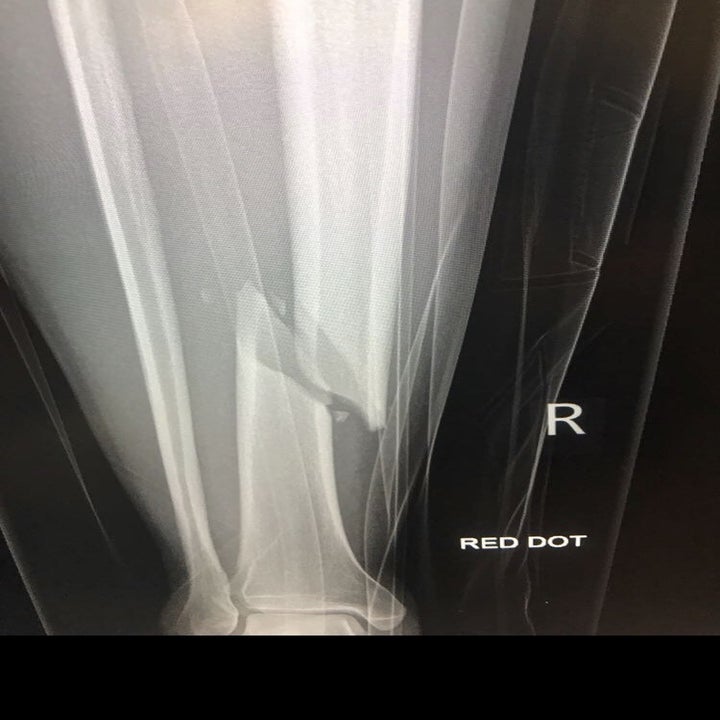

だが、友人の家を出た15分後、ベルハーストは胎児のような姿勢で道に転がっている状態になっていた。右脚の4か所が骨折していた。足首は粉々に砕けていた。彼がマドリードに着くことはなかった。

レントゲン診断の結果、膝から足首にかけて、脛骨と腓骨が複数の場所で完全に折れていることがわかった。脛骨遠位部と脛骨幹部、それに腓骨近位部には転位骨折が見られた。さらに、骨が完全に分断され、どこにもつながっていない骨の断片が散らばっている箇所もあった。足首は粉々に砕けていた。すべてをつなぎあわせるには大手術が必要だった。